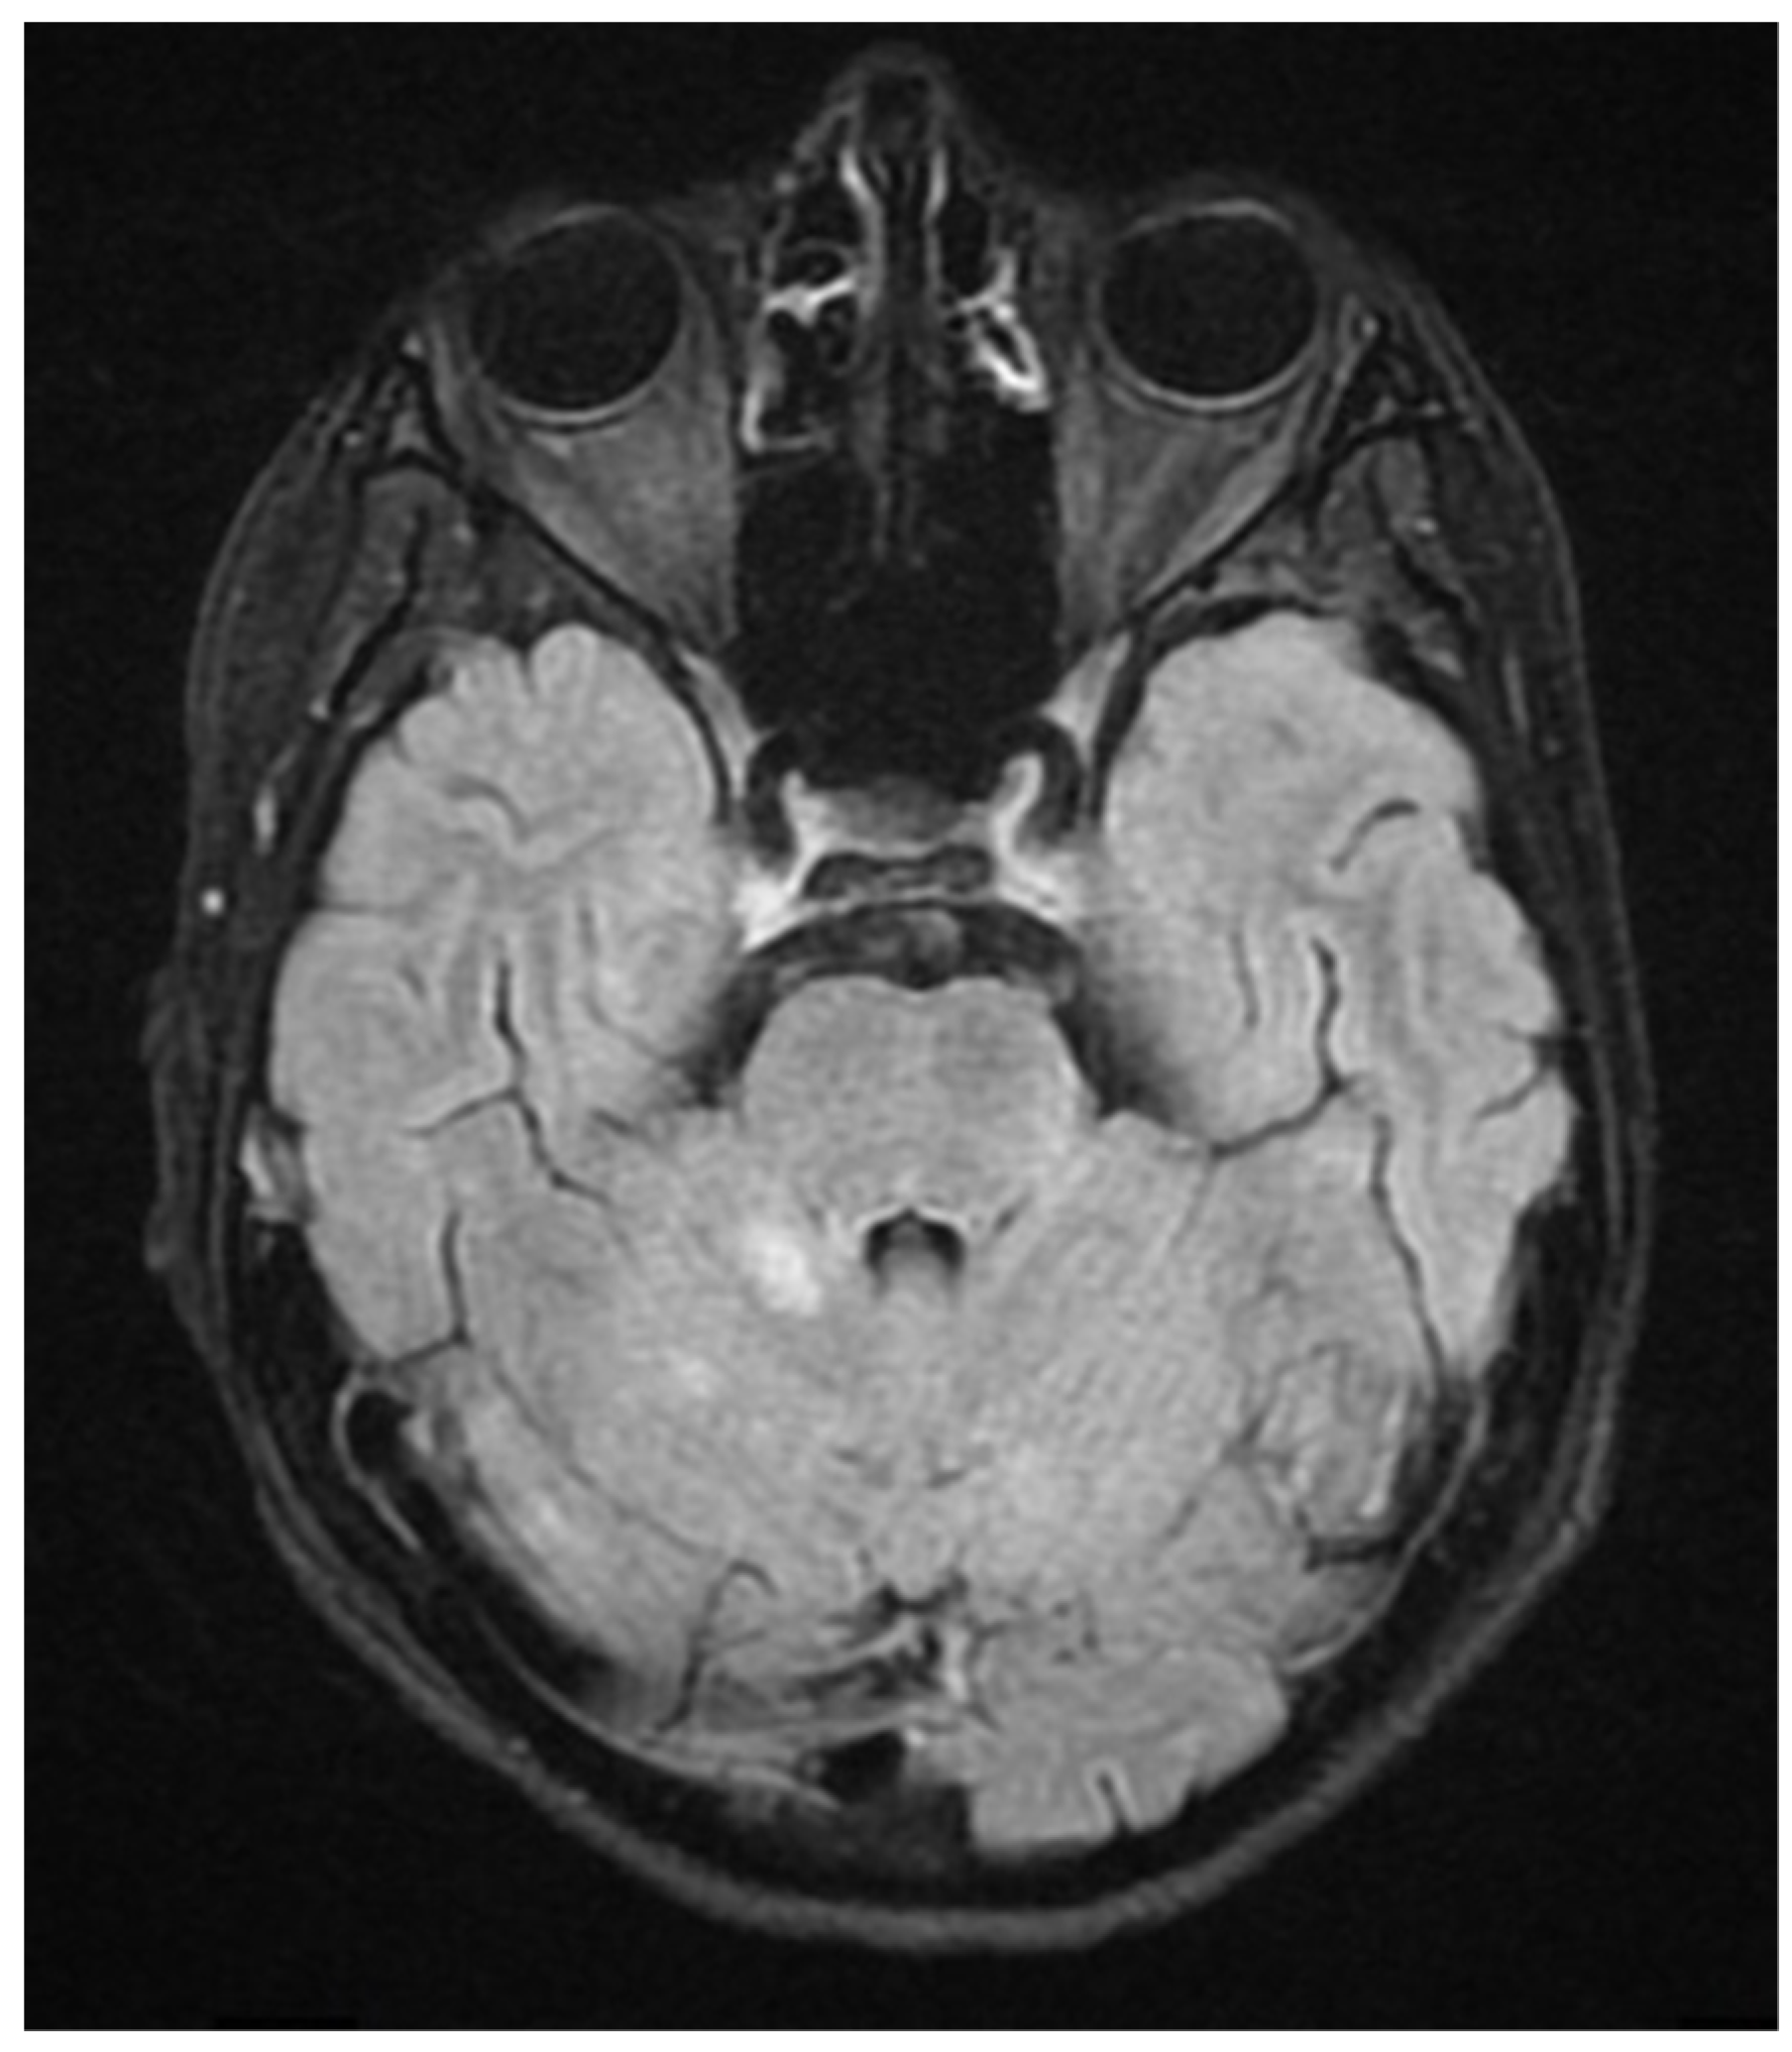

During hospitalization in the neurology ward, Holter EEG was performed in which seizure episodes corresponded to changes in the recording. Interictal EEG showed rapid activity followed by slow theta waves and several sharp and slow wave complexes (Figure 1 and Figure 2). Topiramate was added to valproic acid at a target dose of 2 mg/kg of body weight. Gradual seizure relief was observed in the following weeks, and there were no other neurological manifestations for another nine months. After that time, in December 2021, the patient was admitted to the pediatric ward due to impaired consciousness and persistent vomiting, followed by paresis of the lower limbs. A brain MRI was performed, which showed “T2/FLAIR images reveal poorly defined areas of increased signal in the brain’s white matter, both above and below the tentorium, as well as in the periventricular and subcortical regions. These areas correspond to low signal regions in T1 images. The largest change area measures 19 × 14 mm and is located in the right middle cerebellar peduncle, which merges with changes observed in the pons. Additionally, there is a lesion in the right thalamus, measuring 10 × 24 mm, along with numerous scattered foci in the corona radiata and between the basal nuclei. Overall, the imaging findings primarily suggest acute disseminated encephalomyelitis (ADEM)” (Figure 3 and Figure 4). Cerebrospinal fluid examination revealed oligoclonal bands and an elevated protein level of 118.5 mg/dL (reference range: 15.0–45.0 mg/dL) and a slightly elevated leukocyte level of 29/mm3 (lymphocytes 72.4%, neutrophils 27.6%).

Figure 3.

Transverse FLAIR brain magnetic resonance image showing numerous foci of increased signal between the basal nuclei (December 2021).